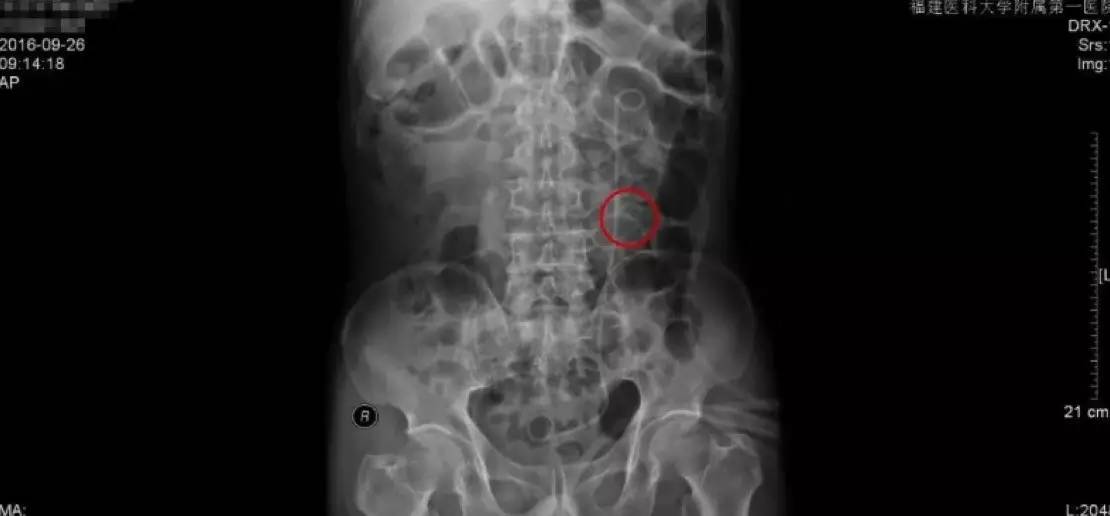

手术前KUB检查报告

手术后KUB检查报告

手术后的复查主要是通过拍KUB,通过与手术前KUB报告的直观对比,从图中可以看到,原来结石的地方,强化的结石已经消失了,左侧可以看到箭头指示的是一根手术后留置的双J管,这根管的目的是为了防止手术后输尿管狭窄黏连。

因为我们的手术是通过输尿管操作的,对输尿管粘膜不同程度有损伤,如果不留置双J管的话,术后容易造成输尿管黏连狭窄,输尿管最细的地方只有0.5cm,所以狭窄是手术后需要注意的并发症。